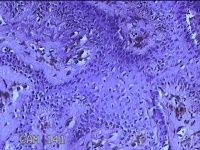

左侧臀部结节

性别

女

年龄

24岁

临床诊断

皮下结节

一般病史

发现左侧臀部结节1年余。

标本名称

大体所见

灰白暗红色带皮肤样结节0.7x0.3x0.2cm一个,表面糜烂,切开结节呈实性,切面灰白暗红色,质软。

图3